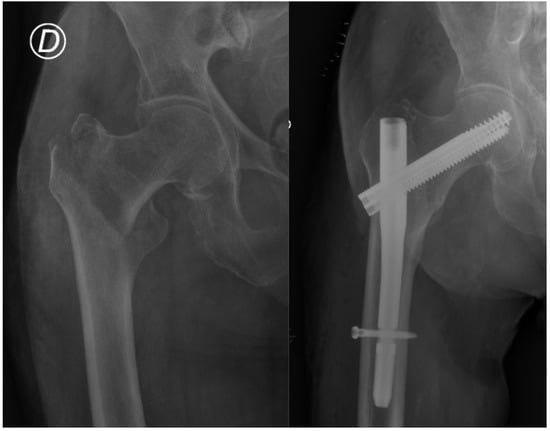

Treatment of Trochanteric Hip Fractures with Cephalomedullary Nails: Single Head Screw vs. Dual Integrated Compression Screw Systems

| Cut-out | 8 (2.1%) | 2 (0.8%) | 6 (4.8%) | 0.016 |